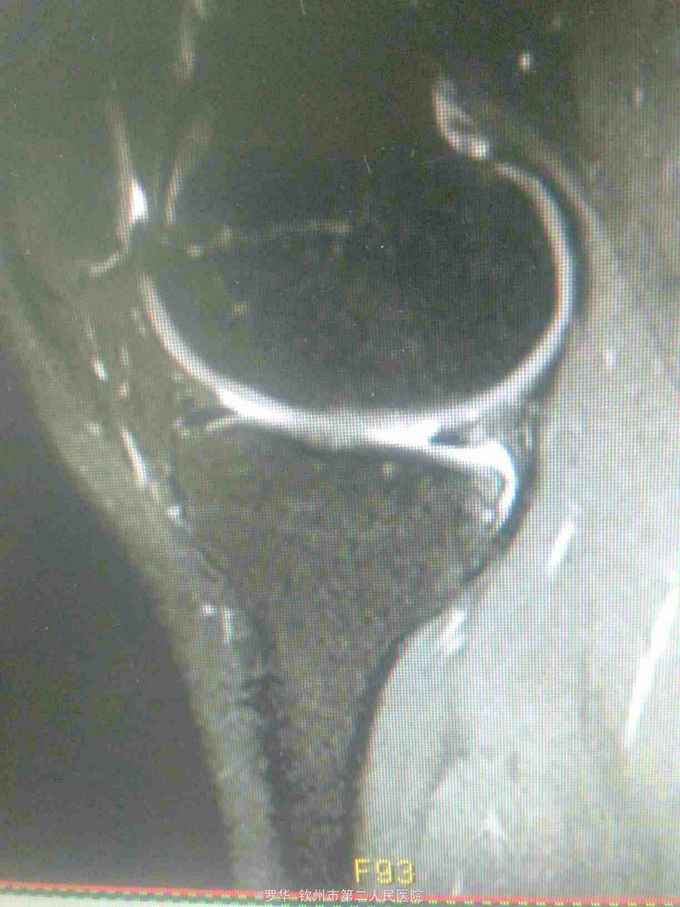

主诉:扭伤致左膝关节活动受限3月余。病史:患者男性,31岁,于入院3月余前扭伤左膝关节,致左膝关节肿痛、活动受限,尚可站立行走,但不能剧烈运动及重体力劳动,曾行磁共振检查提示左膝前交叉韧带损伤,半月板损伤,现为进上一步治疗入院。

查体:左膝关节无明显压痛,前抽屉试验阳性,侧方应力试验、麦氏征、研磨试验均阴性,膝关节屈伸活动可,余查体未见特殊。 辅查:膝关节磁共振提示左前交叉韧带损伤,左膝关节半月板损伤。

诊断:左膝关节前交叉韧带断裂,左膝关节半月板损伤。 治疗:予硬外麻下行左膝关节前交叉韧带重建术。